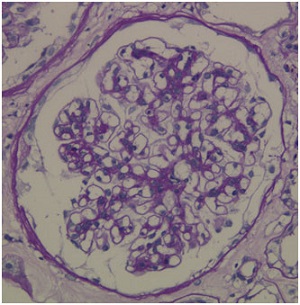

IgA血管炎に伴う腎炎です。血尿、蛋白尿を伴います。IgA血管炎の症状は、紫斑が必ず出現し、腹痛や関節痛を伴うことがあります。診断には腎生検が必要ですが、組織は、IgA腎症と同様の所見を呈します。腎外症状である、紫斑や腹痛などの所見を合わせて診断します。治療としては、副腎皮質ステロイド剤を使用することが多いです。

紫斑、腹痛、関節痛の症状があり、血尿・蛋白尿を伴っていた場合に腎生検を行います。組織所見はIgA腎症と全く同じ所見を呈します。IgA腎症とは、腎臓以外の病変の有無で鑑別します。